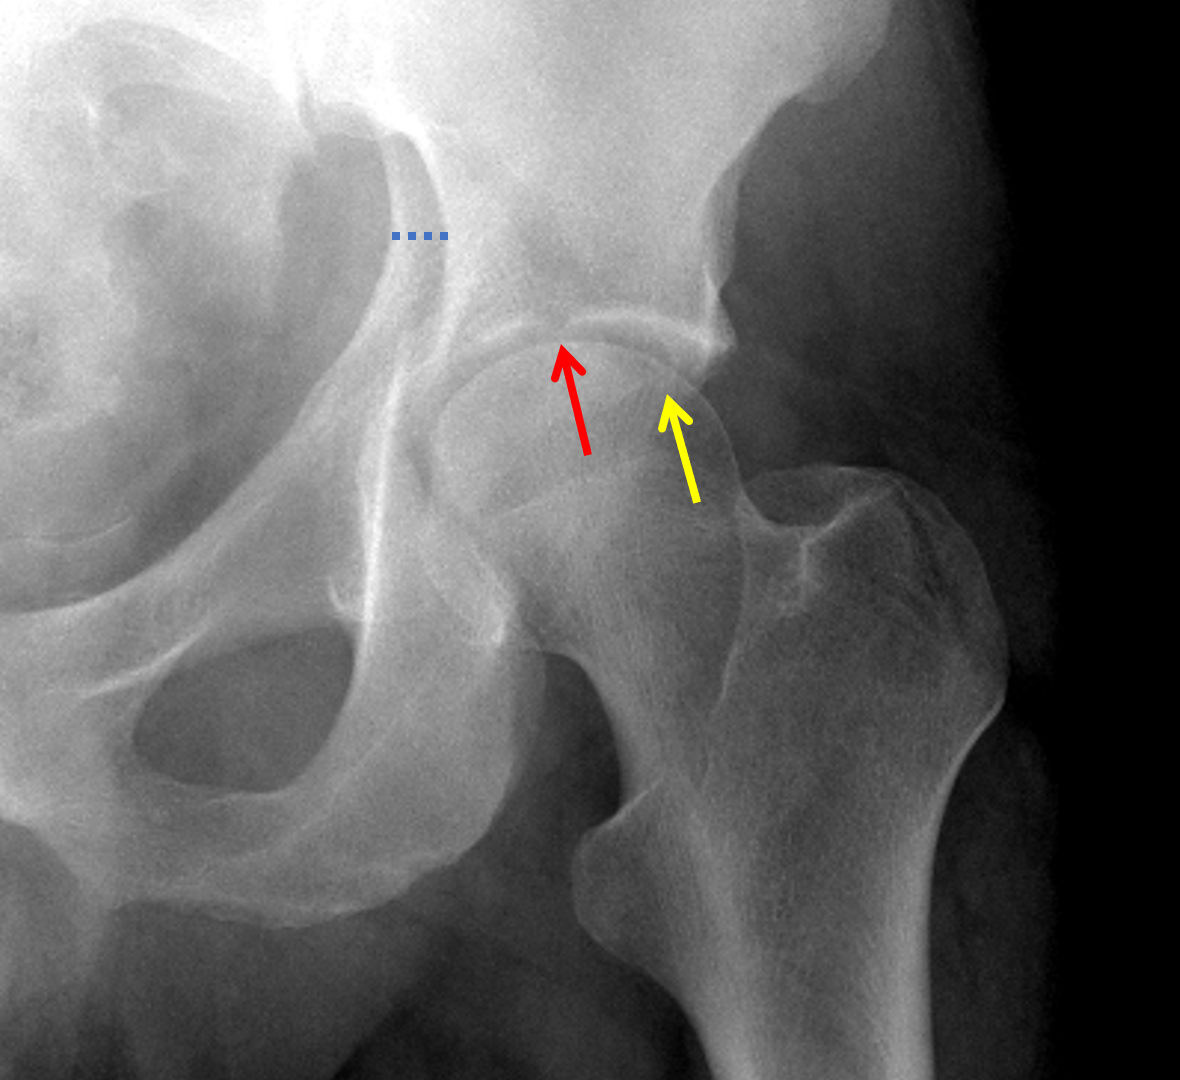

Progress to full weight bearing by 6 to 12 weeks (once adequate fracture healing). Begin with foot-flat partial weight bearing (<10kg) radiographs obtained weekly for the first 4 weeks. Once pain allows, immobilization should follow. įractures treated non-operatively require bed rest initially for comfort. If the CT scan shows no fracture lines involving this area, the fracture can be a candidate for non-operative management displacement cannot exceed 2 mm. Evaluation involves scanning from the vertex to 10mm inferiorly. This system divides fractures into five elementary types and five associated fracture patterns.īoth column with secondary congruence (no traction)Įvaluation of the vertex (the most superior portion of the roof) on CT scan can help identify fractures that are amenable to non-operative management. īy far the most used and most useful classification for acetabulum fractures is that of Letournel. Any evidence of hip subluxation means hip instability.

The patient is supine with the hip extended and in neutral rotation, then the hip is flexed to 90 degrees, and a manual force is applied while taking plain films. Dynamic stress X-rays can also be obtained to evaluate for hip stability, usually when there is a fracture-dislocation involving the posterior wall. 2D images are better used for evaluation of the fracture patterns, while 3D imaging may help less experienced surgeons.

CT axial images are superior to plain radiographs in evaluating the following in acetabulum fractures: Extent and location of acetabular wall fractures, presence of intra-articular fragments, the orientation of fracture lines, the identification of additional fracture lines, rotation of fracture fragments, the status of posterior pelvic ring, and marginal impaction. The advent of CT scans has made the diagnosis and classification of acetabulum fractures much easier. The lateral limb represents the inferior aspect of the anterior wall and the medial limb forms from the obturator canal and the anterior inferior portion of the quadrilateral surface. The teardrop represents a radiographic finding and is not a true anatomical structure. The ilioischial line represents the posterior column, which is a tangency of the quadrilateral surface. The iliopectineal line represents the anterior column and is made up of the pelvic brim and sciatic buttress and greater sciatic notch. The posterior column begins at the superior aspect of the greater sciatic notch, contiguous with greater and lesser sciatic notches, and includes the ischial tuberosity. The anterior column contains the anterior half of the iliac wing that is contiguous with a pelvic brim to superior pubic ramus and anterior half of the acetabular articular surface. The acetabulum divides into an anterior and posterior column. One can visualize the articular surface as an inverted Y with a thick strut of bone connecting it to the sacroiliac (SI) joint, known as the sciatic buttress. Blood supply to the internal surface comes from the fourth lumbar, iliolumbar, and obturator arteries. Blood supply to the external surface is via the superior gluteal artery, inferior gluteal artery, obturator artery, and medial femoral circumflex. The superior portion of the acetabulum articular surface has the name of the weight-bearing dome. The innominate bone forms from the pubis, ischium, and ilium at the triradiate cartilage. Among the most significant advancements has been the advent of percutaneous fixation of certain fracture types. Little has changed since Letournel and Judet’s landmark paper in 1993, and many of their findings remain the “gold standard” for treatment today.